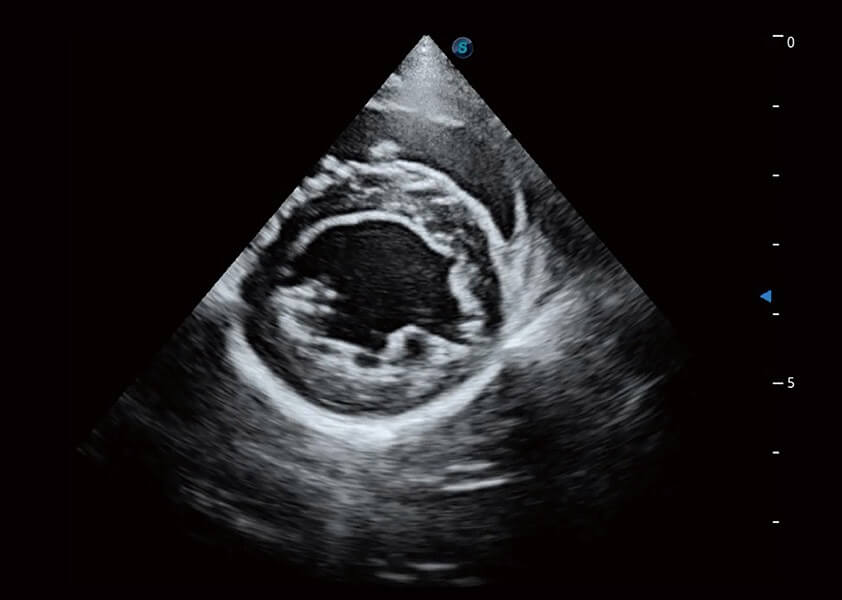

ProPet 60 作为一款高端台式动物超声设备,为动物医生的日常诊断提供了一系列贴合动物临床需求、解决临床实际问题的高级成像功能。凭借全系列高清探头,满足医生对腹部、心脏、生殖、浅表、肌骨等成像的所有需求,切实帮助您提升检查效率,提高诊断信心。

ProPet 60 尊享版

兽用彩色多普勒超声诊断系统